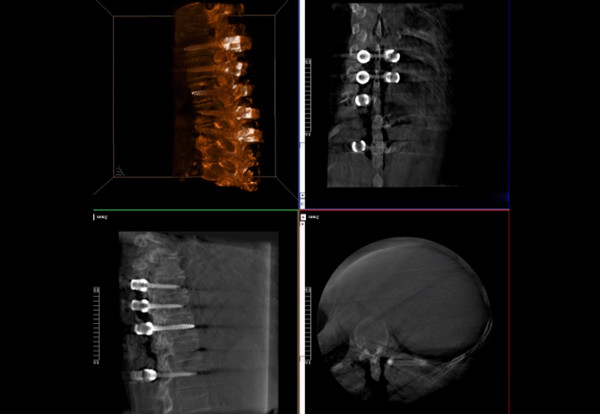

普愛醫療術中三維導航C臂快速生成橫斷面、矢狀面、冠狀面斷層圖像和三維立體圖像,方便醫生確認手術部位。C形臂的大平板帶來出色的顯示視野,可以更好的顯示手術部位全局情況,確保手術規劃及執行的準確性。

三維影像檢驗螺釘植入效果

使用普愛醫療術中三維導航C臂進行透視,根據透視影像引導確認責任間盤、規劃手術方案,充分暴露骨組織,并通過專業器械切除椎板,暴露神經及椎管;在C形臂的引導下,確定責任間盤上下椎體椎弓根位置,制定進針點及進針方向,沿椎弓根方向植入脊柱螺釘進行固定;放入椎間融合器,加固螺釘。最后再進行C形臂透視,確認手術的完成效果。

手術效果確認